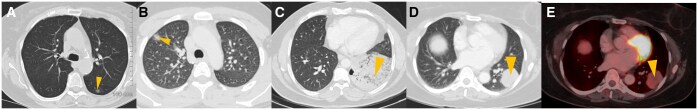

Abstract Image